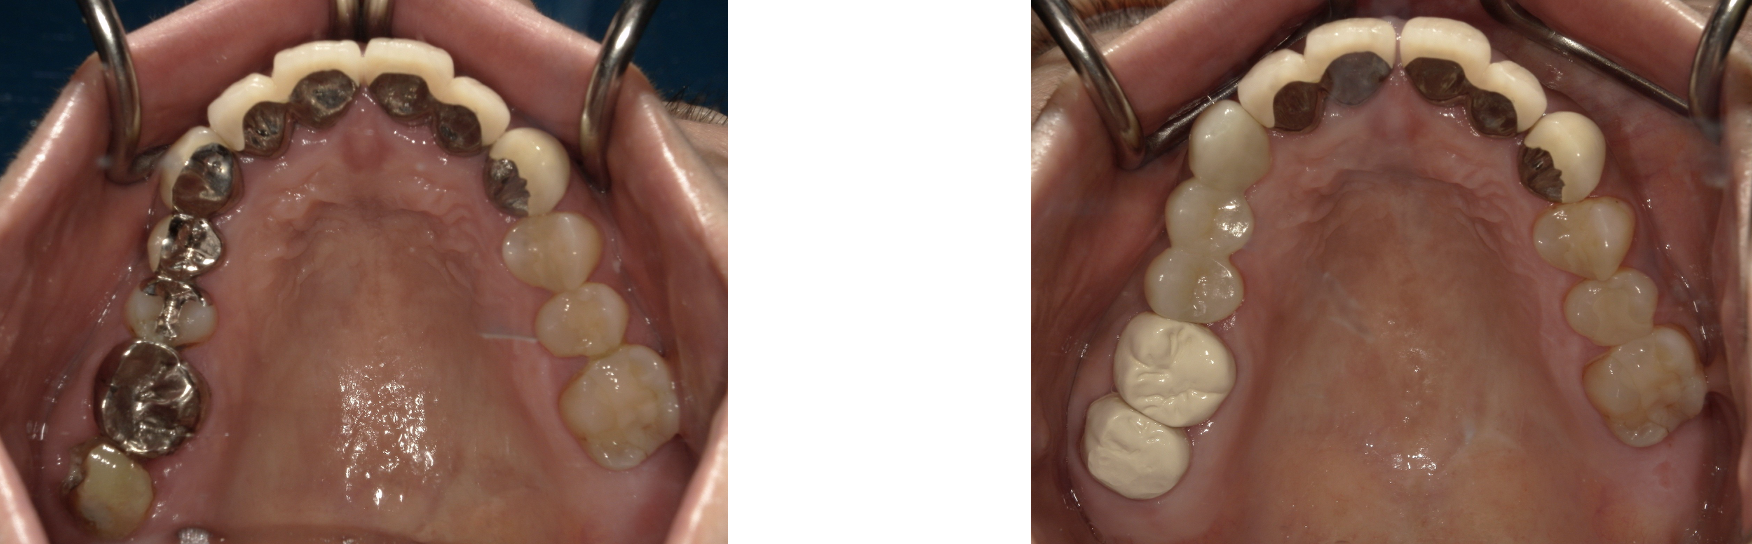

ジルコニアセラミックブリッジ 症例3

右上345番にジルコニアセラミックブリッジを入れた症例